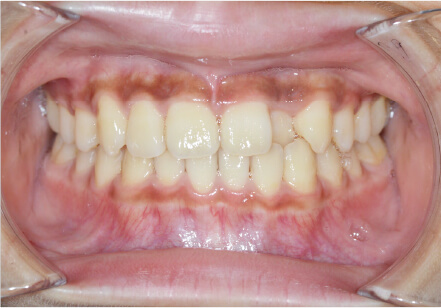

叢生の症例

19歳

/

女性

相談内容

上の前歯が出っ歯、下の前歯がガタガタ

カウンセリング・診断結果

抜歯承諾、IPR承諾、アタッチメント承諾、ミニインプラント承諾、アレルギー有・叢生(凸凹)

治療内容・方法

全顎アライナー矯正 抜歯予定だったが抜歯リスク高いため抜歯なしでIPR量を増やす

術後の経過・現在の様子

クリアライナー

治療のリスク

痛み・歯根吸収・歯肉退縮・虫歯・後戻り

費用・治療期間

880,000円、1年5ヶ月

トレーニングなど